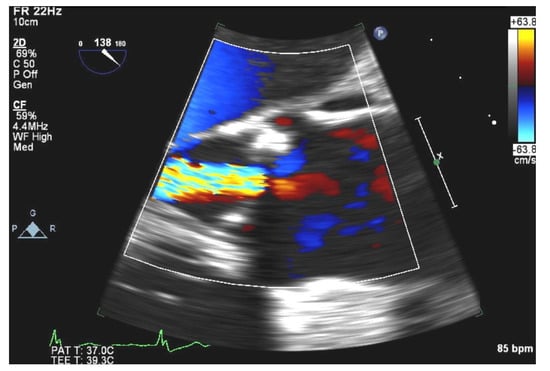

- Manning, W.J.; Weintraub, R.M.; Waksmonski, C.A.; Haering, J.M.; Rooney, P.S.; Maslow, A.D.; Johnson, R.G.; Douglas, P.S. Accuracy of transesophageal echocardiography for identifying left atrial thrombi. A prospective, intraoperative study. Ann. Intern. Med. 1995, 123, 817–822. [Google Scholar] [CrossRef] [PubMed]

- Durmaz, E.; Karpuz, M.H.; Bilgehan, K.; Ikitimur, B.; Ozmen, E.; Ebren, C.; Polat, F.; Koca, D.; Tokdil, K.O.; Kandemirli, S.G.; et al. Left atrial thrombus in patients with atrial fibrillation and under oral anticoagulant therapy; 3-D transesophageal echocardiographic study. Int. J. Cardiovasc. Imaging 2020, 36, 1097–1103. [Google Scholar] [CrossRef] [PubMed]

- Hubbard, E.; Wise, E.; Hubbard, B.; Girard, S.; Kong, B.; Moudgal, V. Tucked away: An infected thrombus. Am. J. Med. 2016, 129, 576–579. [Google Scholar] [CrossRef] [Green Version]